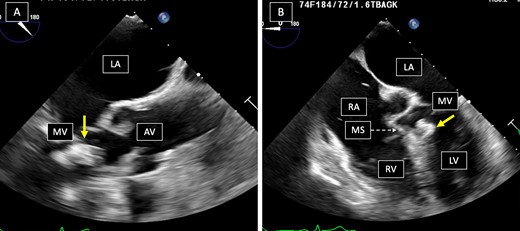

Her physical exam was unremarkable. Laboratory values were notable for a hemoglobin A1c of 6.3%, normal coagulation parameters and negative blood cultures. Chest Röntgenogram and computed tomography scans of her chest were unremarkable. Coronary angiogram demonstrated normal coronary anatomy. A trans-esophageal echocardiogram demonstrated a 10 × 11 mm pedunculated mass with central echolucency in the left ventricle attached by a stalk to the membranous septum near the posteromedial commissure of the mitral valve (Fig. 1) that protruded into the left ventricular outflow tract during systole (Video 1). It also showed severe mitral annular calcification, a normal left ventricular ejection fraction without other valvular pathology and a right-to-left shunt across a patent foramen ovale. We waited several days for the clopidogrel to wear off and, after obtaining consent, brought her to the operating room.

Panel A. Mid-esophageal aortic valve long-axis view, tumor’s relation to the aortic valve is demonstrated. Panel B. Mid-esophageal four-chamber view, tumor’s relation to the mitral valve and the interventricular septum is demonstrated. Arrows point to tumor, LA = left atrium, MV = mitral valve, AV = aortic valve, RA = right atrium, MS = membranous septum, RV = right ventricle, LV = left ventricle.